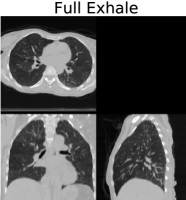

We applied our proposed weighted density registration algorithm to the first subject from the DIR dataset. This subject has images at 10 timepoints and has a set of 300 corresponding landmarks between the full inhale image and the full exhale image. These landmarks were manually chosen by three independent observers. Without any deformation, the landmark error is 4.01 mm (SD 2.91 mm). Using our method, the landmark error is reduced to 0.88 mm (SD 0.94 mm), which is only slightly higher than the observer repeat registration error of 0.85 mm (SD 1.24 mm).

We implement our algorithm on the GPU and plot the energy as well as the Fisher-Rao metric with and without applying the deformation. These results are shown in Figure 6. In this figure, we show that we have excellent data match, while the deformation remains physiologically realistic: inside the lungs there is substantial volume change due to respiration, but the deformation outside the lungs is volume preserving. With a voxel dataset, our algorithm takes approximately nine minutes running for four thousand iterations on a single nVidia Titan Z GPU.